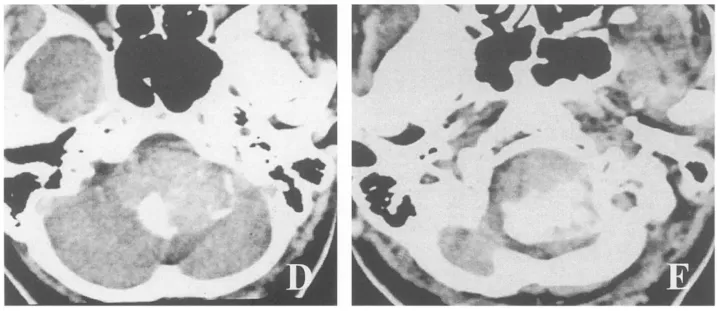

术前MRI与CT评估

CT在显示骨质结构方面较MRI更具优势,部分肿瘤对骨性结构具有侵袭性和破坏性。CT三维成像技术的发展使颅颈交界区骨质结构及血管三维重建成为可能,能够立体直观地显示患者枕骨大孔、寰椎、枢椎等颅底骨质结构及肿瘤与重要血管间的关系,呈现肿瘤周围重要血管、神经、骨质结构的立体空间关系。肿瘤强化明显,呈现典型"瘤染色"特征,有助于指导手术入路选择、骨质移除以及术中肿瘤暴露和保护重要血管神经。